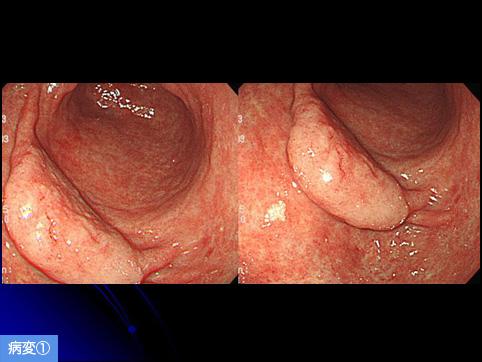

A case of multiple gastric adenomas which mimicked early gastric cancer.

Benign epithelial tumor/Adenoma

Stomach/Antrum

Endoscopy

Type 0/IIa (IIa) Superficial elevated type

20 - 24